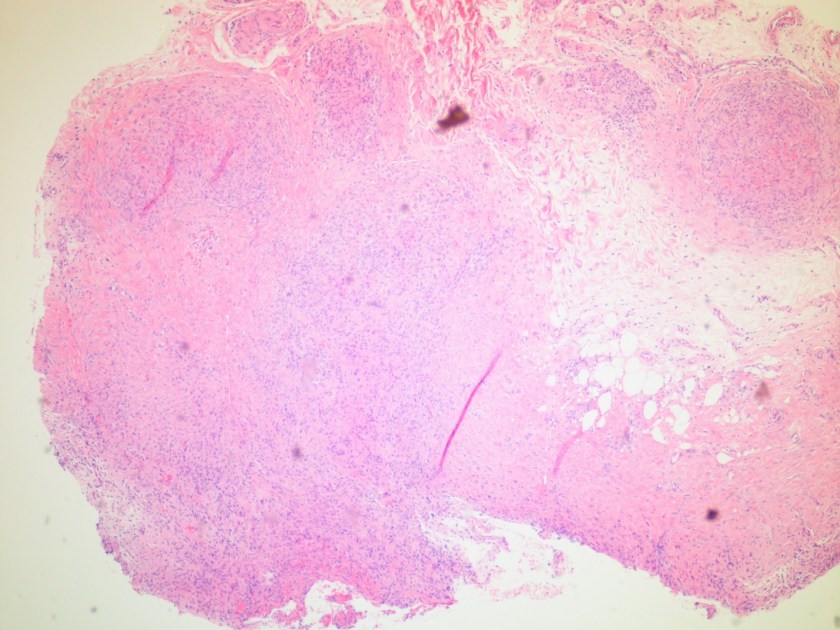

Microscopic examination of the punch biopsy skin specimen revealed a non-caseating granuloma in the deep subcutaneous tissue, with no involvement of the overlying dermis and epidermis (Figure 1). A Kinyoun stain of the tissue showed that the granuloma contained occasional acid-fast bacilli (Figure 2). The bacterial and fungal cultures sent to microbiology were negative. Portions of the specimen used to set up the mycobacterial cultures were incubated in MGITs at 32 and 37°C because the specimen source was skin. The 32°C tube, which was supplemented with hemin, gave a positive signal after 3 weeks of incubation. The Ziehl-Neelsen stain from this tube revealed numerous acid fast bacilli (Figure 3). DNA Gen-Probe analysis was negative for Mycobacterium tuberculosis complex and M. avium-intracellulare (MAI) complex. The organism was identified as M. haemophilum by pyrosequencing.